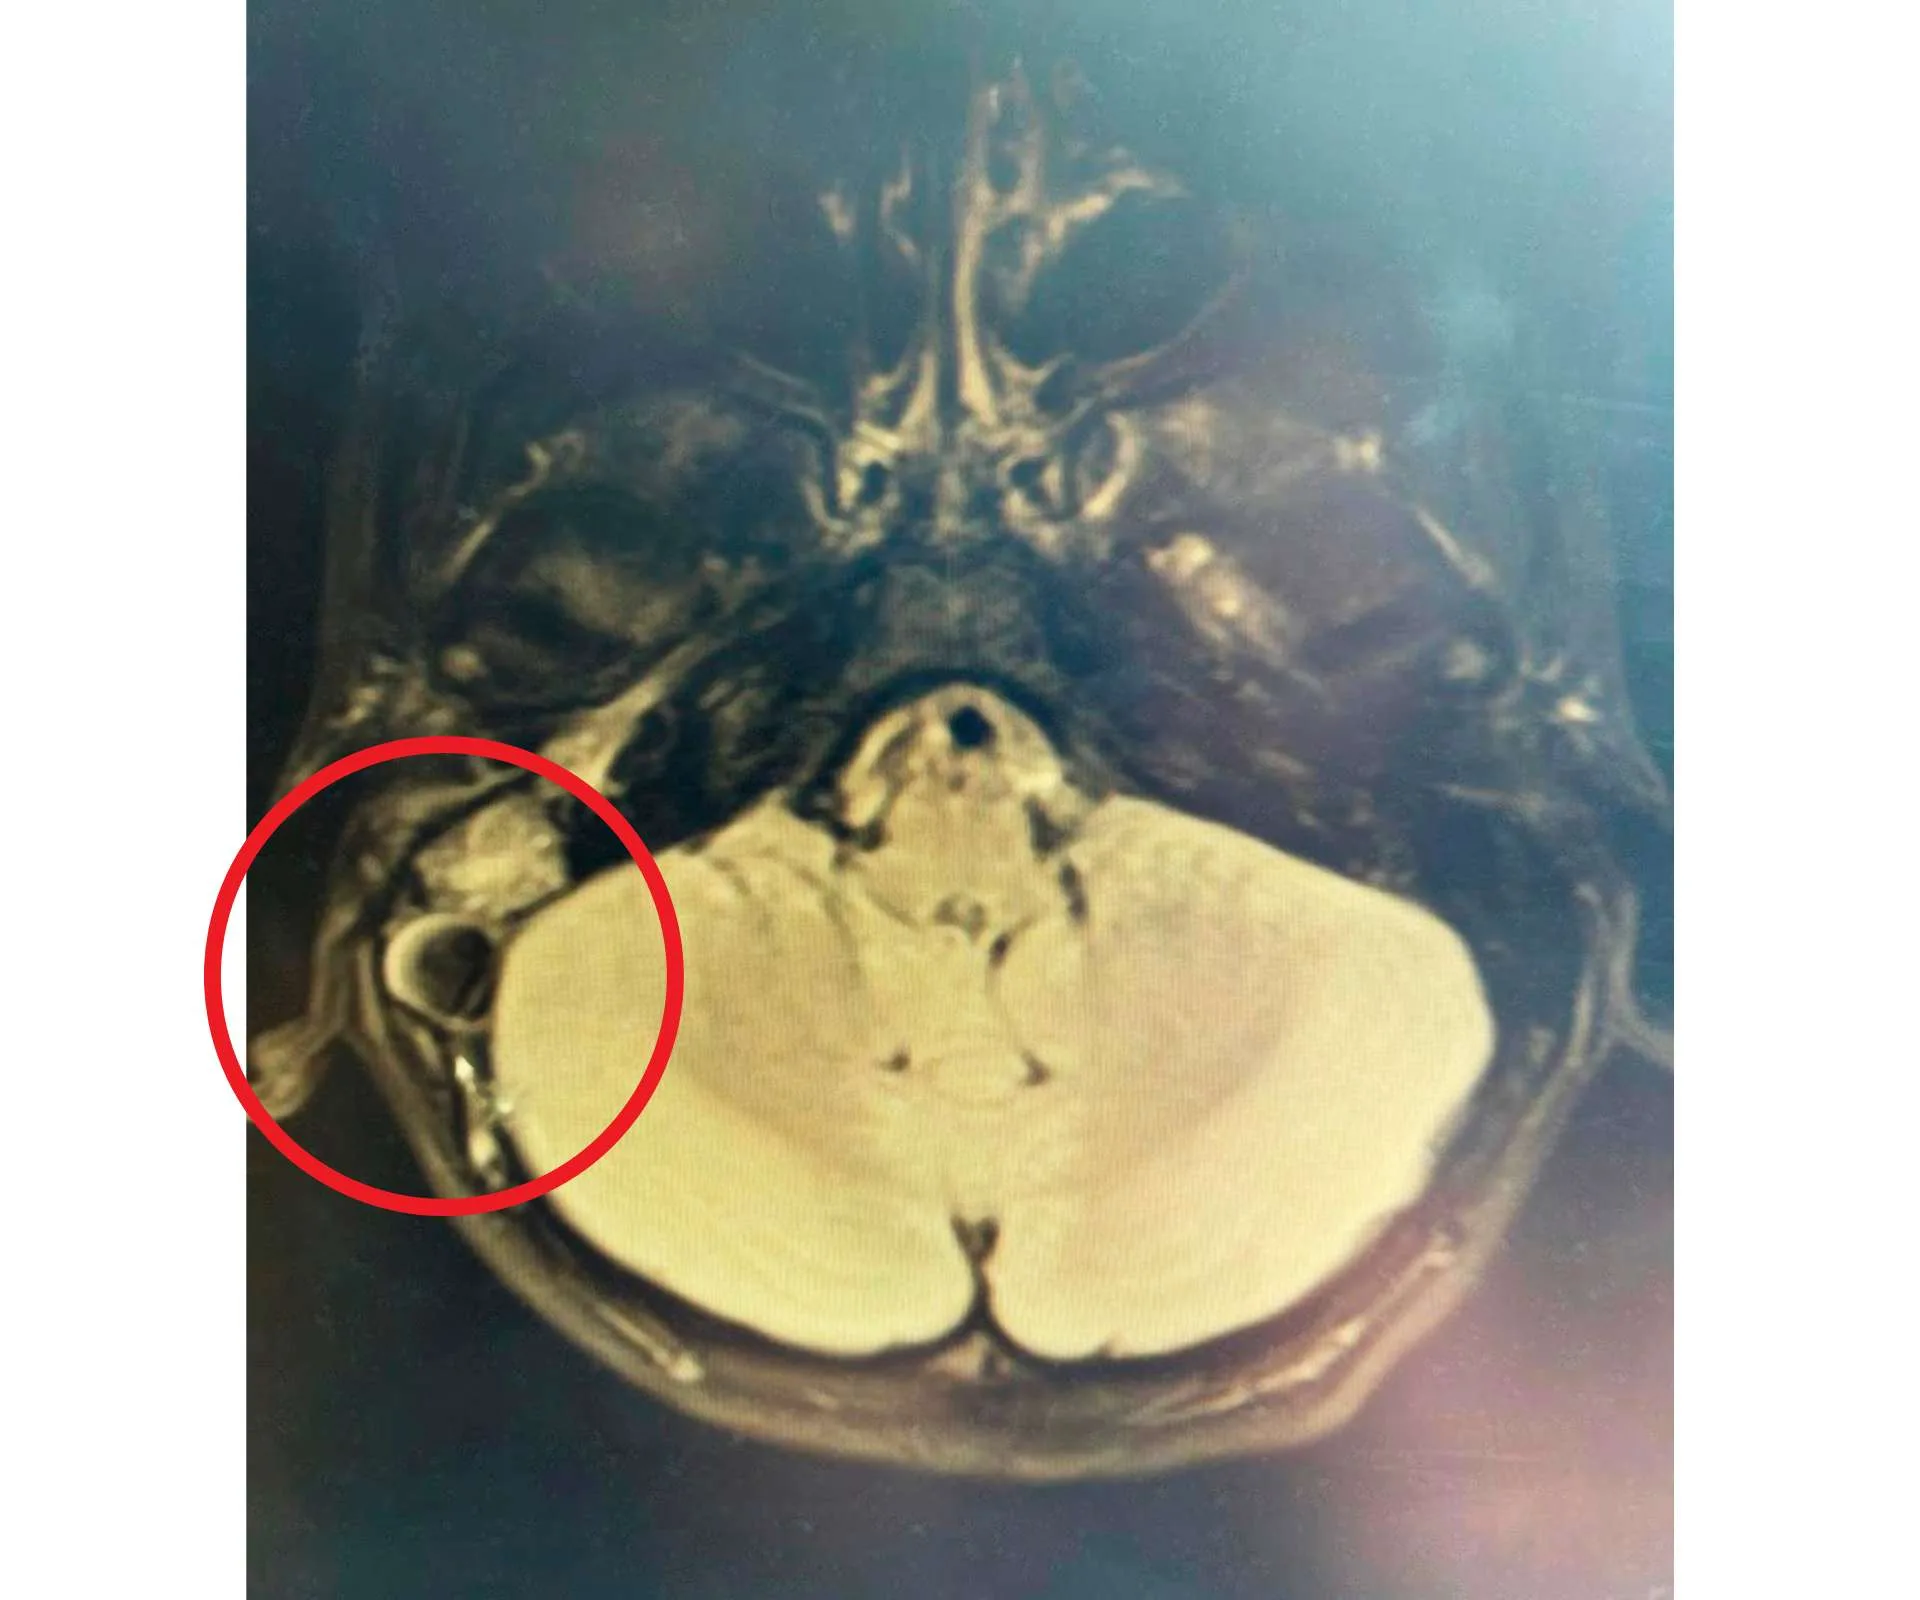

“We were met by a wonderful doctor. After she saw the state of Cole and the distress in my eyes, she sent him straight off for a CT scan. Within half an hour, we had the results. Cole had a massive infection in the mastoid bone behind his right ear, along with clots on his brain. I couldn’t believe it. I asked if he was going to be OK and the doctor didn’t answer.”

Jennifer and Lucas arrived soon after, with his mum saying it was an “intense and overwhelming” experience to see Cole’s bed surrounded by neurology, Ear, Nose & Throat and ICU teams, discussing how best to help him. After an MRI, the medical teams decided to remove the infected part of the mastoid bone to relieve the pressure on his brain, which had formed clots as a protective measure against the infection. They hoped the clots would dissolve naturally once the infection was gone.

“He was put on blood thinners for three months, then a scan showed the clots on his brain had dissolved,” says the doting mum. “It was amazing to hear the doctor say, ‘Cole, you can live your best life now!’”